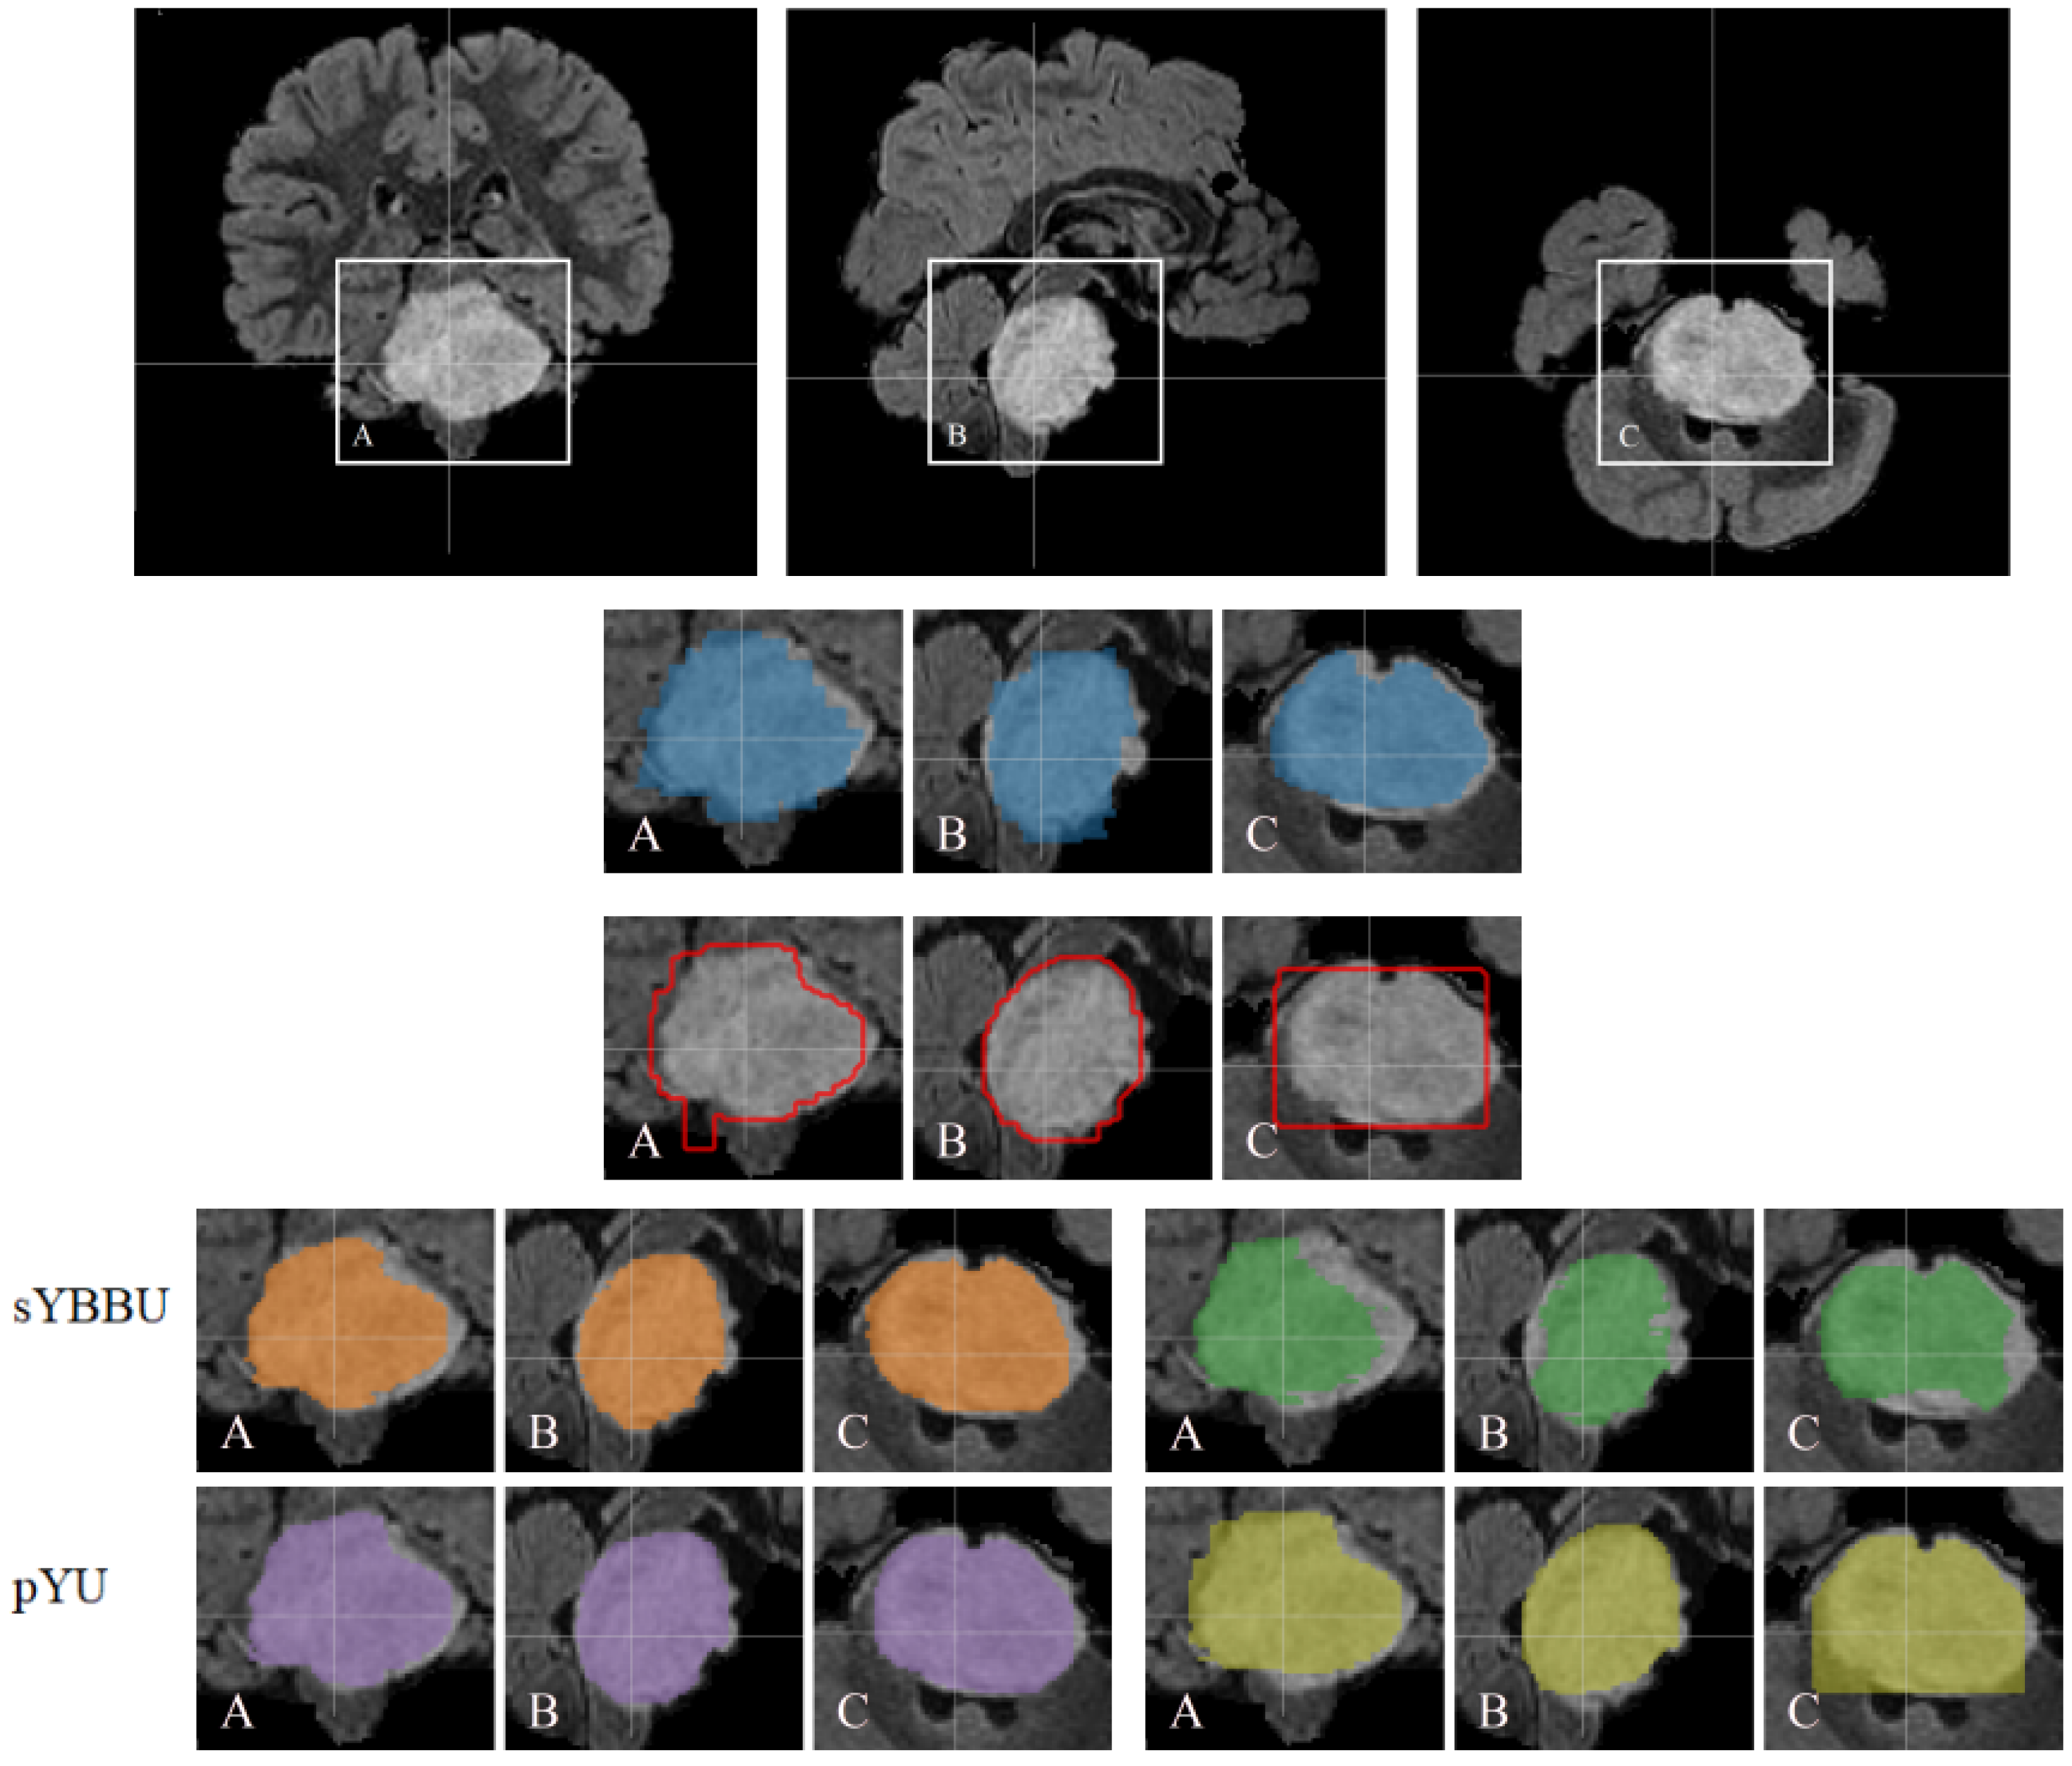

In general, DIPG tumours have a central location involving more than 50% of the pons [8]. On MRI scans and due to its infiltrating nature, the tumour appears as an intrinsic expansion of the brainstem and not as a distinct foreign mass compressing the pons. However, the tumour is not always restricted to the pons and it can infiltrate other compartments of the central nervous system such as the cerebral peduncles and supratentorial midline or the cerebellum [9]. The deformation of the pons induced by the tumour and its infiltrating nature makes its detection and delineation non-trivial. On the T2w scans, the tumour presents a hyper-intense signal while it appears hypo-intense with indistinct tumour margins on T1w scans. Enhancement following gadolinium injection (T1Gd) is inconstant and often absent. Finally, the tumour is relatively homogeneous on FLAIR modality [8]. Figure 1 exhibits a DIPG tumour on different modalities.

DIPG shares some of its visual characteristics with the glioblastoma, especially on T2w and FLAIR modalities. However, glioblastoma presentation differs on T1w and T1Gd, with the absence of a necrosis component in the DIPG, and the gadolinium enhancement which is more intense and always present for the glioblastoma [10]. Our aim is to exploit the existing macroscopic visual similarities of DIPG with glioblastoma or low-grade gliomas, to train a two-step robust model able to infer DIPG segmentations.

Figure 1. Top row: Example of T2w MRI scan of a patient with DIPG tumour extending beyond the pons. (a) Axial, (b) Coronal and (c) Sagittal slices. Bottom row: Example of glioblastoma and DIPG MRI scans, in axial slices. (d) glioblastoma T2w, (e) glioblastoma FLAIR, (f) DIPG T2w and (g) DIPG FLAIR.